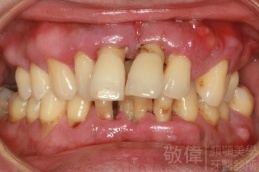

人工植牙/因嚴重牙周病而缺牙的植牙重建

嚴重牙周病   拔除牙周病牙齒